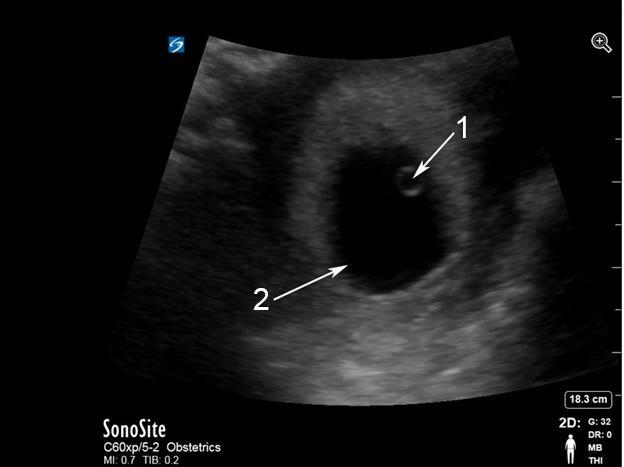

Escaneo endovaginal pélvico – Imagen de saco gestacional con saco vitelino

1. Saco vitelino (Yolk Sac)

2. Saco gestacional (Gestational Sac)